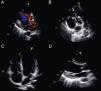

A 27-year-old-man was admitted with fever and elevated inflammatory parameters, attributed to multiple small lung abscesses. At admission a continuous systolic–diastolic murmur was heard from the left sternal edge to the apex. Workup included transthoracic echocardiography, which revealed a restrictive perimembranous ventricular septal defect (VSD) (velocity 4.89 m/s) partly covered by a previously unknown typically aneurysmal tricuspid valve (TV) (Figure 1A and B). A vegetation was present on the atrial side of the TV (Figure 1C), but there was also an image suggestive of vegetation attached to the VSD (white arrow). Aortic valve involvement with two vegetations and severe regurgitation was also demonstrated (Figure 1D).

Transthoracic echocardiography. (A) Parasternal long-axis view with color Doppler disclosing a left-to-right shunt through a ventricular septal defect (VSD). (B) Parasternal short-axis view showing lack of support of the aortic valve, leading to a diagnosis of perimembranous VSD, vegetation attached to the atrial side of the tricuspid valve, and aneurysmatic image of the tricuspid valve, difficult to distinguish from a vegetation attached to the membranous portion of the VSD. (C) Apical 4-chamber view confirming the presence of the vegetation attached to the atrial side of the tricuspid valve. (D) Parasternal long-axis view displaying the vegetations attached to the right and non-coronary aortic cusps.